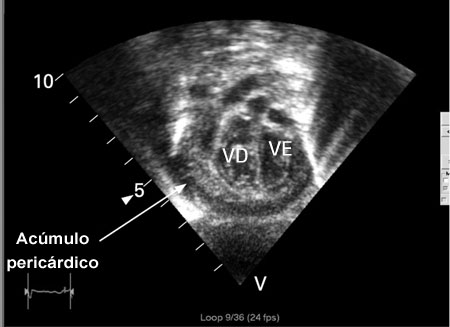

[Figure caption and citation for the preceding image starts]: Ecocardiografia em um bebê com pericardite purulenta, mostrando uma coleção pericárdica. VE = ventrículo esquerdo, VD = ventrículo direitoKaruppaswamy V, Shauq A, Alphonso N. BMJ Case Reports 2009; doi:10.1136/bcr.2007.136564 [Citation ends].